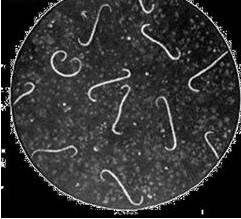

细螺旋体病